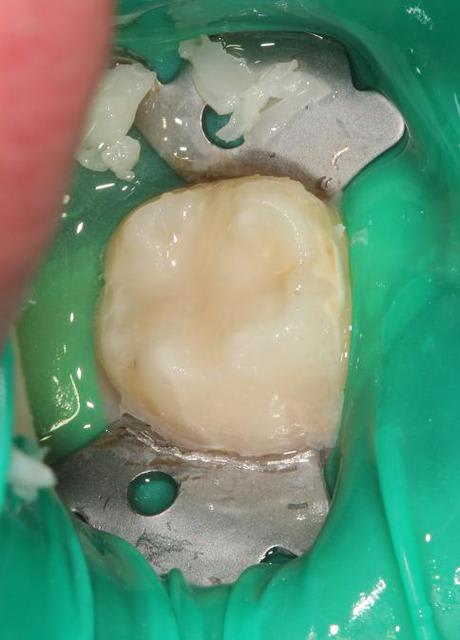

Quelques photos pour illustrer le sujet initial. Dommage que ces dents n'aient jamais eu de sealants.

Pour l'effraction pulpaire sur dent asymptomatique, je fais le protocole que Choixpeau avait mis sur le forum : hypochlorite puis adhésif directement au contact. Aucun problème à court terme pour le moment.

Si effraction plus importante : MTA.